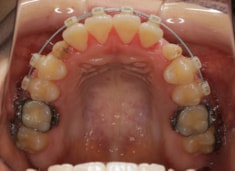

治療中